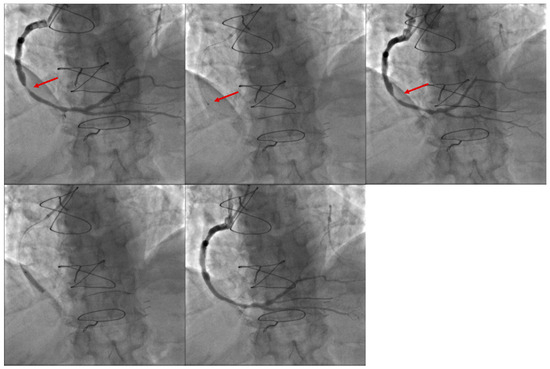

21 pages, 2629 KB

Article

Three-Year Follow-Up of the First 100 Patients Treated with the Balloon-Expandable Myval Transcatheter Aortic Valve System: A Single-Centre Experience

by Balázs Magyari, Bálint Kittka, Ilona Goják, Gábor Kasza, Kristóf Schönfeld, László Botond Szapáry, Mihály Simon, Rudolf Kiss, Andrea Bertalan, Edit Várady, Péter Mátrai, István Szokodi and Iván Horváth

J. Clin. Med. 2025, 14(21), 7883; https://doi.org/10.3390/jcm14217883 - 6 Nov 2025

Viewed by 587

Abstract

Background/Objectives: To report our single-centre experience with the first 100 patients who underwent transcatheter aortic valve replacement (TAVR) with the new balloon-expandable Myval system. We report 3-year outcomes in low- to high-risk TAVR patient populations. Methods: From November 2019 to July 2021, 100 [...] Read more.

Background/Objectives: To report our single-centre experience with the first 100 patients who underwent transcatheter aortic valve replacement (TAVR) with the new balloon-expandable Myval system. We report 3-year outcomes in low- to high-risk TAVR patient populations. Methods: From November 2019 to July 2021, 100 consecutive patients underwent TAVR, and their outcomes were classified according to the Valve Academic Research Consortium 3 definitions. Device performance was assessed using transthoracic echocardiography. Data collection was approved by the local ethical committee. Results: Among the 100 patients, most were male (n = 63), the mean age was 74.7 years, the mean EuroSCORE II score was 4.8 ± 4.9, and the mean Society of Thoracic Surgeons score was 5.6 ± 3.9. All patients were followed up for three years or until death. The rates of all-cause mortality, cardiac mortality and stroke were 28%, 7% and 5%, respectively. After three years, residual moderate aortic regurgitation was detected in eight patients without severe grade, and bioprosthetic valve dysfunction was observed in 17: structural valve deterioration in 10 (only stage 2), non-structural valve deterioration in three (paravalvular leak in one, patient–prosthesis mismatch in two), and endocarditis in four. Definite transcatheter heart valve thrombosis (hypoattenuated leaflet thickening) was not observed. Bioprosthetic valve failure was detected in four patients (stage 1: 1, stage 2: 0, stage 3: 3). After three years of follow-up, survival analysis revealed no significant differences in all-cause mortality, cardiac mortality, or the composite endpoint (including cardiac mortality, stroke and valve-related dysfunction) between patients with bicuspid (BAV) and tricuspid (TAV) aortic valve morphology and across annulus sizes (small, intermediate and large). Conclusions: TAVR resulted in significant and sustained improvements in valve haemodynamics with low rates of valve dysfunction and adverse clinical outcomes over a three-year follow-up period. Valve morphology (BAV vs. TAV) and annulus size did not significantly impact survival, haemodynamic performance, or valve durability. These results support the expanded use of TAVR in diverse patient populations, although extended follow-up is essential to fully establish long-term durability. Full article

Show Figures

Figure 1